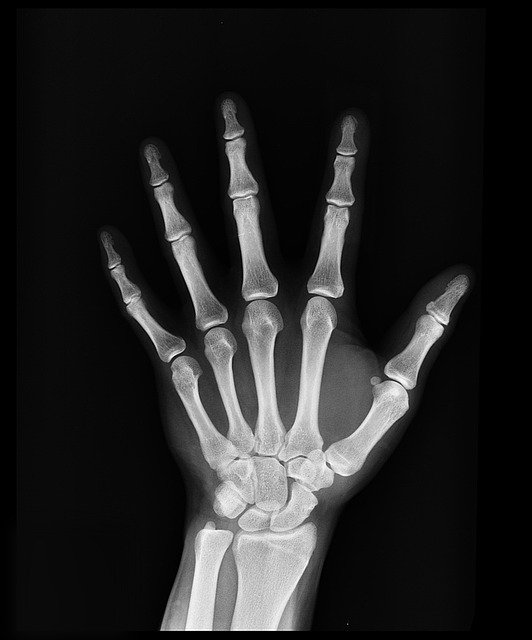

성장판 검사 방법은 많지만 가장 정확한 방법은 X-ray 촬영입니다.

X-ray로 성장판을 검사하면 손이나 골반, 무릎관절, 팔꿈치관절, 발목관절을 사용해서 골연령을 평가하는데요.

신체의 여러 뼈 중에 왼쪽 손목을 X-ray 촬영하는 것이 가장 정확한 검사 방법입니다.

손목뼈는 뼈조직이 만들어지는 순서가 일정하고 다른 부위의 사진과 비교해도 정확도가 떨어지지 않는데다가 촬영이 용이하기 때문이죠.